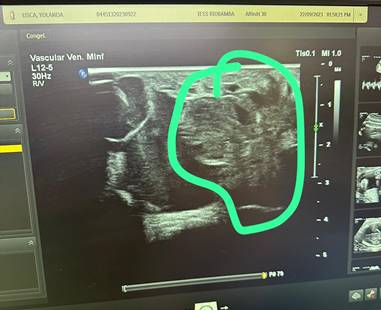

Se practica ecografía Doppler en modo B, con transductor lineal, a través del cual se detecta abundante contenido hemático en compartimiento anterior y lateral de la pierna, con imagen característica de quistes multitabicados Figura B, además se realiza una flebografía ascendente en la cual se evidencia que no existen fistulas arteriovenosas Figura C. En la Angiotac se descarta dependencia o comunicación con grandes vasos Figura D, por tanto, se diagnostica Malformación Vascular: Linfangioma.

Descripción: Descripción: Descripción: C:\Users\VALE\AppData\Local\Microsoft\Windows\INetCache\Content.Word\4d245231-4d21-43e7-a881-2e5aee3e3105.jpg

Figura B. Ecografía modo B con transductor lineal en el cual se evidencia abundante contenido hemático.